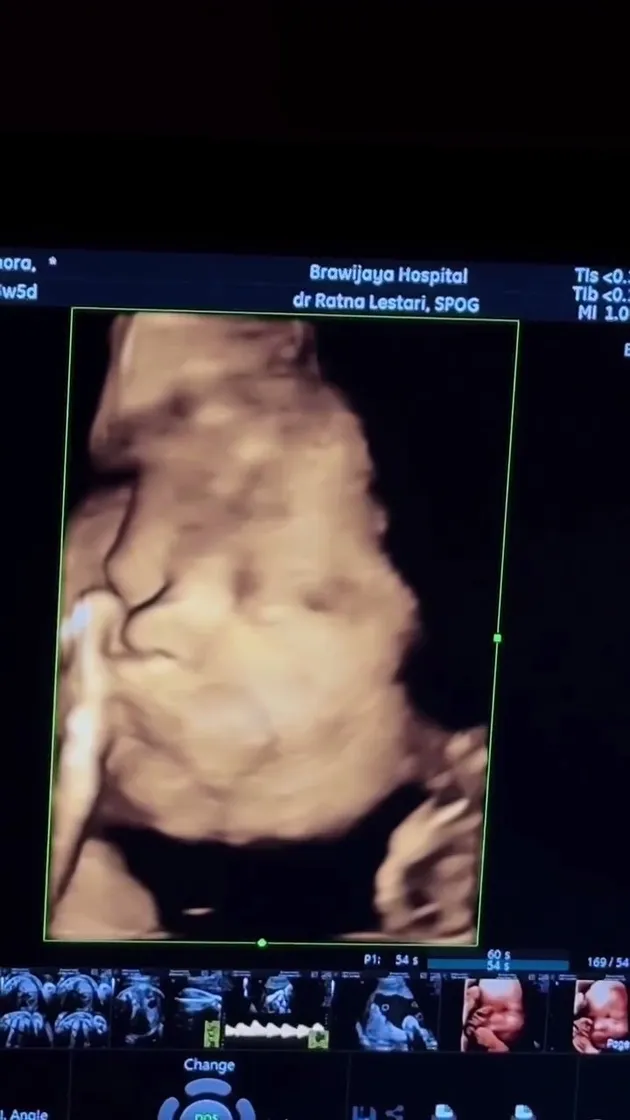

Steffi Zamora once again captured public attention through a special moment ahead of the birth of her first child with Nino Fernandez. Through a post on social media, Steffi showcased a moment of herself undergoing an ultrasound examination in the third trimester of her pregnancy.

In the photos shared, Steffi appears to be smiling happily as she looks at the ultrasound results showing the face of her future child. Here are the moments of the artist.